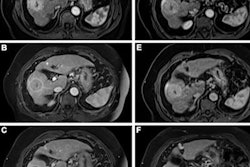

They collected real-life logistic data from 62 breast MRI screening exams conducted at three different hospitals. The data were imported using 3D simulation software (FlexSim Healthcare). The group then designed and tested a series of different scenarios composed of combinations of different layouts, staff composition, scanning protocols, equipment (e.g., dockable vs. nondockable tables), and number of changing rooms.

"Screening within these modeled facilities was simulated for a time span of three months, with opening hours from 8:00 to 18:00 and variations in patient arrival patterns," Koco and colleagues noted. "The model provided several realistic, virtual, logistical pathways for MRI screening, and their outcome measures like patient throughput and waiting times."

The baseline scenario, simulated using the existing workflow steps and recourses, had a total average appointment time of 25 minutes and 54 seconds, of which the MRI room was occupied for just over 19 minutes. On average, 36 patients per day could be screened.

The group's optimum scenario was a 390 sq. m. facility layout focused on patient communication, workflow, accessibility, and accommodating dockable tables. Implementing a suitable patient arrival pattern, using an abMRI, and implementing other changes resulted in an average appointment time of 19 minutes and 36 seconds, of which the MRI room was occupied for 6 minutes and 21 seconds.

"Having three radiographers and four changing rooms (with dockable tables) seemed to be most efficient approach, leading to a throughput of around 67 patients per day," they stated. "Perfusion-only scanning protocol reduces table time from 12 minutes and 49 seconds to 5 minutes and 42 seconds."